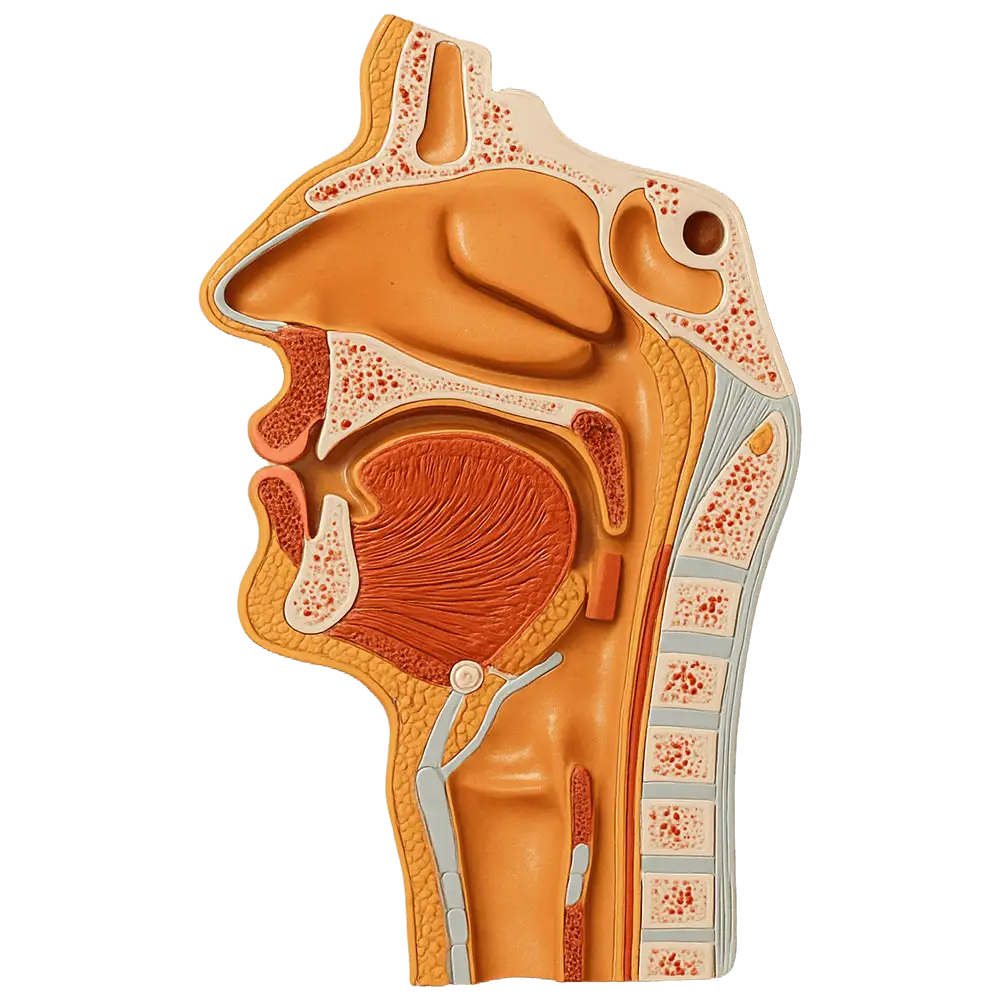

Zastajanje hrane prilikom gutanja je simptom koji nikako ne treba zanemariti, jer može ukazivati na niz različitih medicinskih stanja. Prvi korak u dijagnostici je pregled ORL specijaliste, koji će proceniti stanje ždrela, grkljana i početnog dela jednjaka, uz moguće uključivanje gastroenterologa radi dodatne evaluacije.

ORL specijalista je prvi lekar kome bi trebalo da se obratite ukoliko imate osećaj da vam hrana zastaje u grlu. Kroz klinički pregled, eventualnu endoskopiju i funkcionalne testove, moguće je brzo otkriti uzrok tegoba.

U određenim slučajevima, posebno kada ne postoji jasno vidljiv uzrok ili kada su simptomi udruženi sa poremećajima koordinacije prilikom gutanja, može biti potreban i neurološki pregled. To je važno kako bi se isključila neurološka oboljenja koja utiču na motornu funkciju mišića uključenih u gutanje.

Na prvom mestu, potrebno je isključiti postojanje mehaničke prepreke, kao što je benigni ili maligni izraštaj, koji ometa normalan prolazak hrane kroz ždrelo ili jednjak. ORL pregled, često dopunjen endoskopijom ili radiološkim metodama, može pomoći u brzom otkrivanju takvih promena.

U praksi, kod velikog broja pacijenata, zastajanje hrane nastaje bez postojanja stvarne anatomske prepreke. Kod ovih osoba se najčešće radi o tzv. cervikalnoj disfagiji, koja potiče iz regiona vrata.

Refluksna bolest u ovom obliku dovodi do iritacije sluznice grla i jednjaka zbog vraćanja želudačne kiseline i enzima, što može izazvati osećaj nelagodnosti i otežanog prolaska zalogaja.